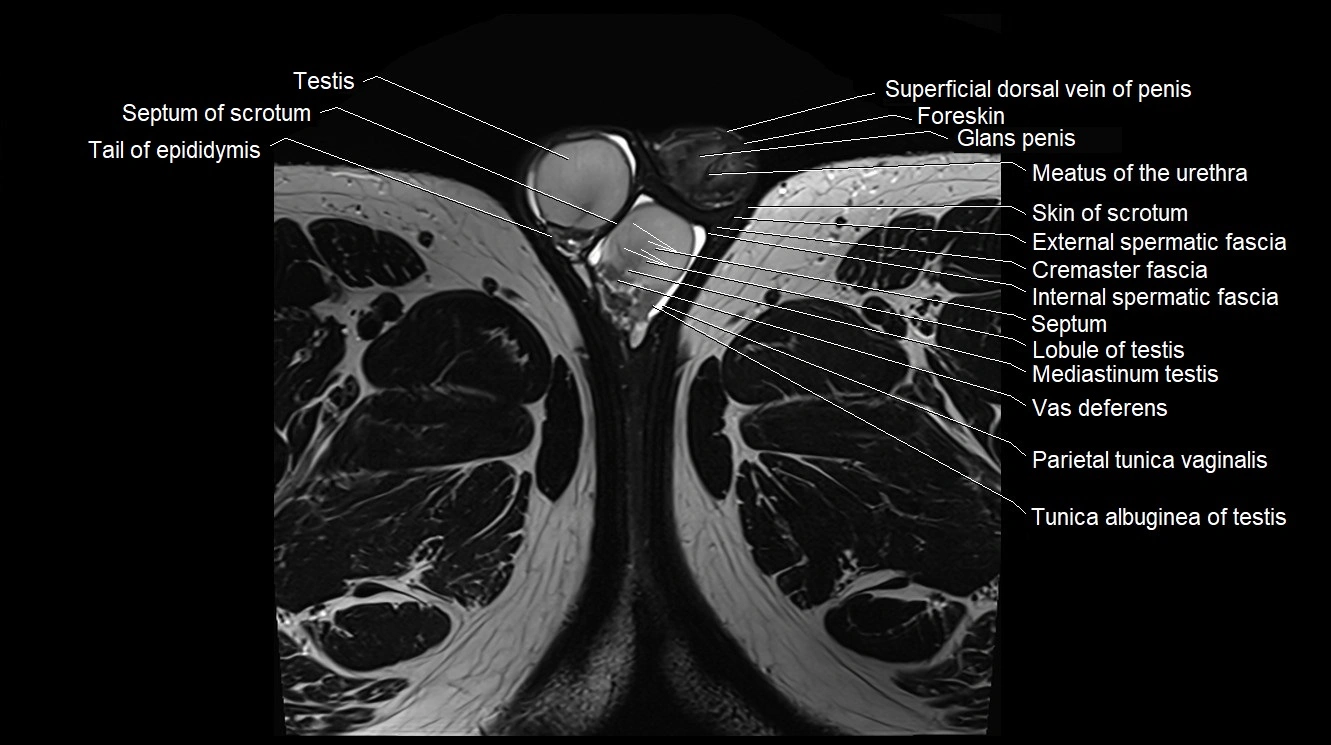

MRI image